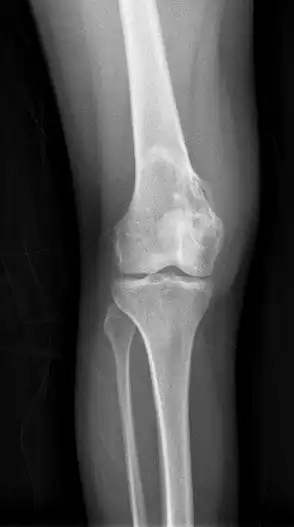

| Chondrosarcoma long bone of thigh near knee | |

Imaging studies - including radiographs ("x-rays"), computerized tomography (CT), and magnetic resonance imaging (MRI) - are often used to make a presumptive diagnosis of chondrosarcoma.[11] However, a definitive diagnosis depends on the identification of malignant cancer cells producing cartilage in a biopsy specimen that has been examined by a pathologist. In a few cases, usually of highly anaplastic tumors, immunohistochemistry (IHC) is required.

Imaging